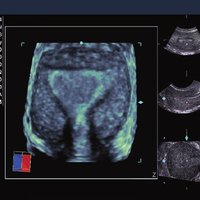

Siemens ACUSON X300 PE Beschreibung

• Features: 3D, 4D, Farb/Doppler